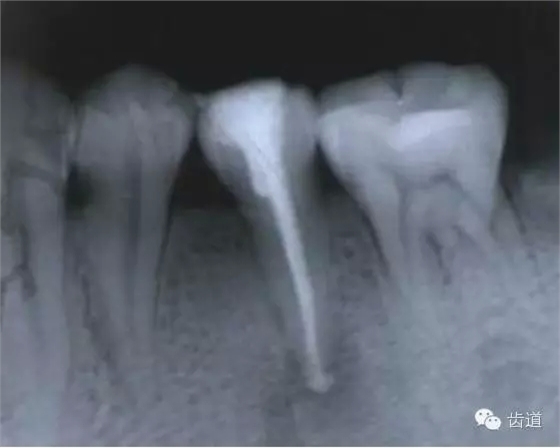

(3)髓室底穿孔:處理方法同上。同時(shí)找到根管口,按常規(guī)進(jìn)行根管預(yù)備和充填。如穿孔范圍太大易導(dǎo)致根分歧病變,予后欠佳??尚懈芡饪啤?/span> (4)根管壁形成臺(tái)階:先換小號(hào)銼去除臺(tái)階,再順序擴(kuò)挫。如根管壁穿孔,找到主根管進(jìn)行預(yù)備后,主根管及側(cè)穿道同時(shí)充填。在根尖1/3或根尖彎曲處側(cè)穿,根充后,配合根尖手術(shù)——根切+倒充填。 (三)髓腔壁穿孔的預(yù)防 1.掌握每個(gè)牙齒的髓腔解剖形態(tài)及其在牙齒表面的投影范圍。 2.術(shù)前拍X線片。 3.進(jìn)行規(guī)范化操作,隨時(shí)與X線片核對(duì)器械進(jìn)入方向及進(jìn)入深度。 器械折斷在根管內(nèi),阻塞根管,妨礙治療操作。如不能取出,使根管治療不能繼續(xù)進(jìn)行,不得不輔以根尖手術(shù)。 左上7近中頰根器械折斷 右上6腭根器械折斷 1.器械本身的原因 材料質(zhì)量欠佳,受力后易折斷。 器械反復(fù)使用,產(chǎn)生折痕,用力后也易折斷。 消毒方法不當(dāng),消毒液中未放防銹劑,器械銹蝕易折。 2.術(shù)者器械使用不當(dāng) 遇有阻力,仍強(qiáng)行進(jìn)入,用力過(guò)大過(guò)猛,超過(guò)了器械所能承受的程度 未按操作要求使用器械(跳號(hào)) 器械在細(xì)窄根管內(nèi)被卡住后,仍勉強(qiáng)旋轉(zhuǎn)器械柄 折斷于根管內(nèi)的器械要盡量取出,若無(wú)法取出經(jīng)常規(guī)充填后,成功率不受明顯影響。 1.折斷器械有一部分露在根管口外,用鑷子或持針器夾取出。 2.器械斷端在根管口內(nèi):用超聲根管銼在該器械旁增隙,通過(guò)超聲震蕩和沖洗,可將折斷器械從根管內(nèi)震動(dòng)沖出。在手術(shù)顯微鏡下直視操作,大大提高了取出的成功率。 3.折斷器械尖端已超出根尖孔:無(wú)癥狀不處理;有疼痛則作根尖手術(shù)取出。 4.折斷器械較長(zhǎng),各種方法均不能取出,可作根管電解消毒,塑化治療或塑化劑處理,根管充填。 若患牙根尖有病變,必要時(shí)作根尖切除+倒充填。 1.使用前認(rèn)真檢查器械有無(wú)生銹、折痕、螺紋松解等現(xiàn)象。 2.嚴(yán)格按器械使用規(guī)則進(jìn)行操作。 3.使用機(jī)用根管器械,應(yīng)支點(diǎn)穩(wěn)、轉(zhuǎn)速慢,并只能應(yīng)用于直的根管。 4.制備開(kāi)髓洞形時(shí),應(yīng)充分暴露根管口,對(duì)彎曲根管能盡量減少其彎曲度,對(duì)彎曲度在30o以上的根管盡量采用超聲根管預(yù)備并使用鎳鈦根管挫。 5.控制器械使用次數(shù):根管銼刃部的鋒利程度隨所預(yù)備的根管數(shù)目增加而降低。 25#以下器械只能用1—2次,30#—50#器械可用二次。 牙折分為冠折、根折及冠根折三種。根管治療后,由于牙折導(dǎo)致拔除者屢見(jiàn),故應(yīng)引起足夠重視。 (一)牙折發(fā)生原因 1.經(jīng)根管治療的牙齒,因失去了牙髓的營(yíng)養(yǎng)而脆性增大。 2.制備開(kāi)髓洞形時(shí),過(guò)多的磨除了牙體組織,削弱了牙體組織強(qiáng)度。 3.根管清理和成形以及做冠樁預(yù)備過(guò)程中,過(guò)多的磨除根管壁,削弱了牙根強(qiáng)度。 4.用牙膠做根管充填時(shí),側(cè)向或垂直壓力過(guò)大,均可造成牙根縱折。 5.其他:根管釘、樁的采用;熱塑冷凝的牙膠尖填入根管后自身體積膨脹;牙周受累的牙齒,支持骨喪失,也增加了牙折的機(jī)會(huì)。 (二)牙折的處理 應(yīng)盡可能保存患牙 1.冠折:根據(jù)折斷的牙體組織的多少及部位,可分別選擇充填;加螺旋釘固位;全冠或樁冠修復(fù)。 2.冠根折:折斷線在齦下不足3mm,配合齦切術(shù)或冠延長(zhǎng)術(shù),將斷端暴露在齦上,然后根據(jù)缺損情況考慮冠修復(fù)的種類。 折斷線在齦下超過(guò)3mm,患牙牙根較長(zhǎng),正畸力將牙根牽引,無(wú)條件做正畸治療的單根牙則拔除,多根牙則可做截根或半切除術(shù)。 3.根橫折:在冠方1/3處理方法同冠根折。 在根中1/3根折線不與牙周袋相通,做根內(nèi)固定,加牙冠部夾板固定4—8周。在根尖1/3,調(diào)合 解除創(chuàng)傷力,如有癥狀做根尖切除術(shù)。 4.根縱折:?jiǎn)胃绖t拔除;多根牙做截根術(shù)或半切除術(shù)。也有報(bào)告,用切開(kāi)翻瓣暴露縱折牙根,粘接劑粘合裂根的方法保留縱折牙牙根,若以后出現(xiàn)牙周袋則拔除。 (三)牙折的預(yù)防 1.根管治療過(guò)程中,有薄壁銳尖或陡峭的無(wú)基釉質(zhì),應(yīng)及時(shí)降低咬合或磨除。根管治療后,常規(guī)調(diào)合。 2.根管治療應(yīng)遵循:在保證治療的前提下,盡量保留健康的牙體組織。 3.根管充填操作用力適度。 五、下唇麻木 (一)發(fā)生原因:主要由下齒槽神經(jīng)損傷所致 1.治療操作中藥物、器械或根充物超出根尖孔,進(jìn)入下頜管損傷下齒槽神經(jīng) 2.解剖因素:下頜牙齒根尖距下頜管太近,有些牙根與下頜管相連,以下頜第二恒磨牙多見(jiàn) 左下7根充后下唇麻木 左下5根管預(yù)備后下唇麻木 (二)處理: 1.根據(jù)病史認(rèn)真查找原因,如為炎癥刺激所致,應(yīng)積極治療根尖周炎,加口服營(yíng)養(yǎng)神經(jīng)藥物。 2.理化刺激所致,口服營(yíng)養(yǎng)神經(jīng)藥物。 (三)預(yù)防: 1.作根管治療前拍X線片,下頜牙齒應(yīng)特別注意與下頜管的關(guān)系。 2.準(zhǔn)確測(cè)量根管工作長(zhǎng)度,各種操作均在工作長(zhǎng)度范圍內(nèi)進(jìn)行。根管封藥不可過(guò)飽和,防止藥液溢出根尖孔。 此種意外發(fā)生,給患者帶來(lái)很大的精神壓力,如器械落入呼吸道,則增加更大的痛苦,應(yīng)慎重處理。 (一)發(fā)生原因 1.術(shù)者精神不集中 2.患者過(guò)于緊張不合作 3.患者體位不正確 4.器械從手中滑脫 (二)處理 1.醫(yī)護(hù)人員應(yīng)鎮(zhèn)靜,安撫患者。 2.立即拍腹部平片。 3.落入消化道應(yīng)住院觀察。 4.服用長(zhǎng)纖維及有潤(rùn)滑作用的食物,勿服瀉藥。 5.適當(dāng)走動(dòng),勿劇烈運(yùn)動(dòng)。 6.每天拍腹部X線片,檢查大便至排出。 7.落入呼吸道,應(yīng)請(qǐng)耳鼻喉科或胸外科醫(yī)生協(xié)助取出。 (三)預(yù)防: 1.針對(duì)原因預(yù)防。 2.治療時(shí)上橡皮障。 3.無(wú)條件用橡皮障,可在器械柄拴安全鏈。 皮下氣腫是根管治療中少見(jiàn)的并發(fā)癥 (一)臨床表現(xiàn) 根據(jù)患牙的部位不同,可分別出現(xiàn)在頰部、頸部、和眶周等疏松軟組織迅速腫脹、充血,有捻發(fā)音。捻發(fā)音是組織氣腫的病理特征,以此和其他腫脹做鑒別。如空氣向頸部移動(dòng)可引起呼吸困難。 (二)發(fā)生原因 1.用壓縮空氣吹干根管時(shí)間過(guò)長(zhǎng)。 2.使用過(guò)氧化氫液沖洗根管,將藥液壓出根尖孔。 不可加壓??! (三)處理 一般不需特殊治療,給予抗生素預(yù)防感染 上頜竇曲霉病、上頜竇疼痛、上頜竇炎癥等。 根管治療的各種并發(fā)癥,絕大多數(shù)情況是由術(shù)者操作不規(guī)范所致。在根管治療過(guò)程中,術(shù)者應(yīng)嚴(yán)格按照規(guī)程進(jìn)行每一步操作,這些并發(fā)癥是完全可以避免的。